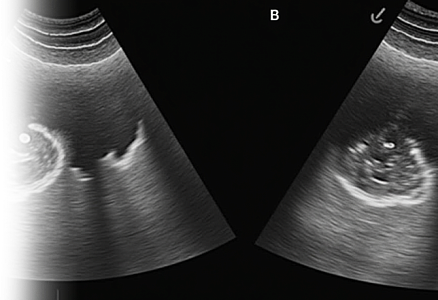

УЗИ аноректальной области

УЗИ аноректальной области – важный метод ультразвукового исследования, который позволяет оценить состояние тканей и органов в области аноректального канала и выявить различные заболевания и патологии.